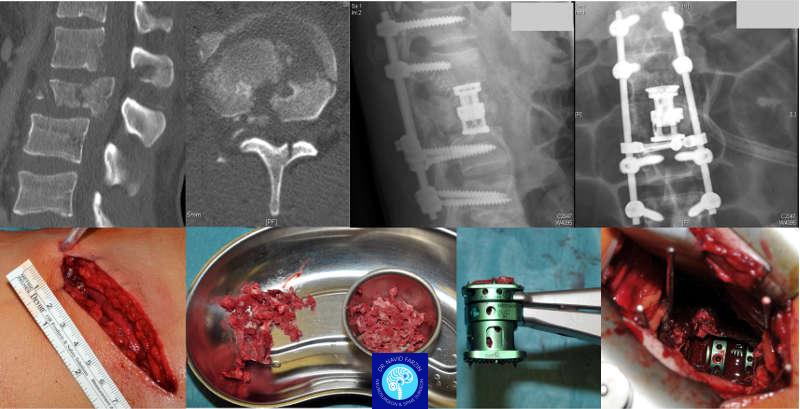

روشهای جدید جراحی شکستگی ستون فقرات

در شیراز، بسته به نوع شکستگی، این روشها کاربرد دارند:

۱. جراحی کمتهاجمی (MISS)

برای شکستگیهای پایدار یا فشاری، با برش کوچک و آسیب حداقل به بافتها.

۲. کیفوپلاستی و ورتبروپلاستی

تزریق سیمان پزشکی برای بازسازی و تثبیت مهره، مناسب برای شکستگیهای ناشی از پوکی استخوان.

۳. تثبیت مهرهها با پیچ و پلیت (Spinal Fusion)

برای شکستگیهای ناپایدار یا جابهجایی مهرهها.

در این روش مهرهها بهصورت پایدار به هم متصل میشوند.

۴. جراحی باز در شکستگیهای شدید

برای مواردی که فشار مستقیم روی نخاع وجود دارد و نیاز به آزادسازی اعصاب است.

۲. تسلط بر تکنیکهای نوین جراحی

دکتر فرزین از روشهای کمتهاجمی، فیوژن پیشرفته، تثبیت مهرهها با پیچ و پلیت، و در برخی موارد کیفوپلاستی و ورتبروپلاستی استفاده میکنند.

۳. تشخیص دقیق با بررسی MRI و معاینه عصبی کامل

دقت در تشخیص و انتخاب روش مناسب جراحی، مهمترین عامل در جلوگیری از عوارض بعدی است.

رویکرد ایشان بر اساس استانداردهای علمی و تجربه ۱۲ ساله بالینی است.